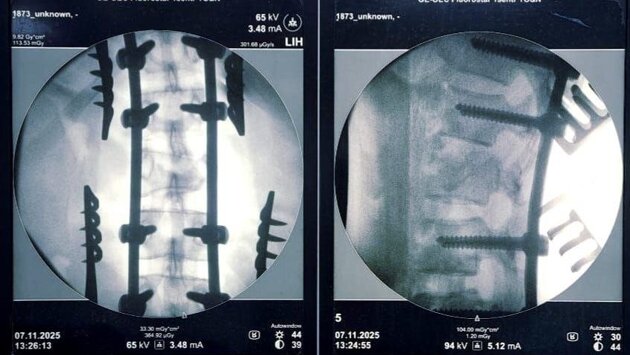

Пациентке диагностирована сочетанная травма: тупая травма грудной клетки, ушиб левого легкого, закрытый неосложненный перелом ребра слева, повреждение позвонков, сдавление спинного мозга с нарушением функций тазовых органов, – сообщил нейрохирург Александр Попов.

Была проведена операция – спинной мозг высвобожден из сдавления, восстановлены конфигурация сломанного позвонка и ось позвоночника, проведена стабилизация позвоночного столба металлоимплантами. Она длилась более двух часов.